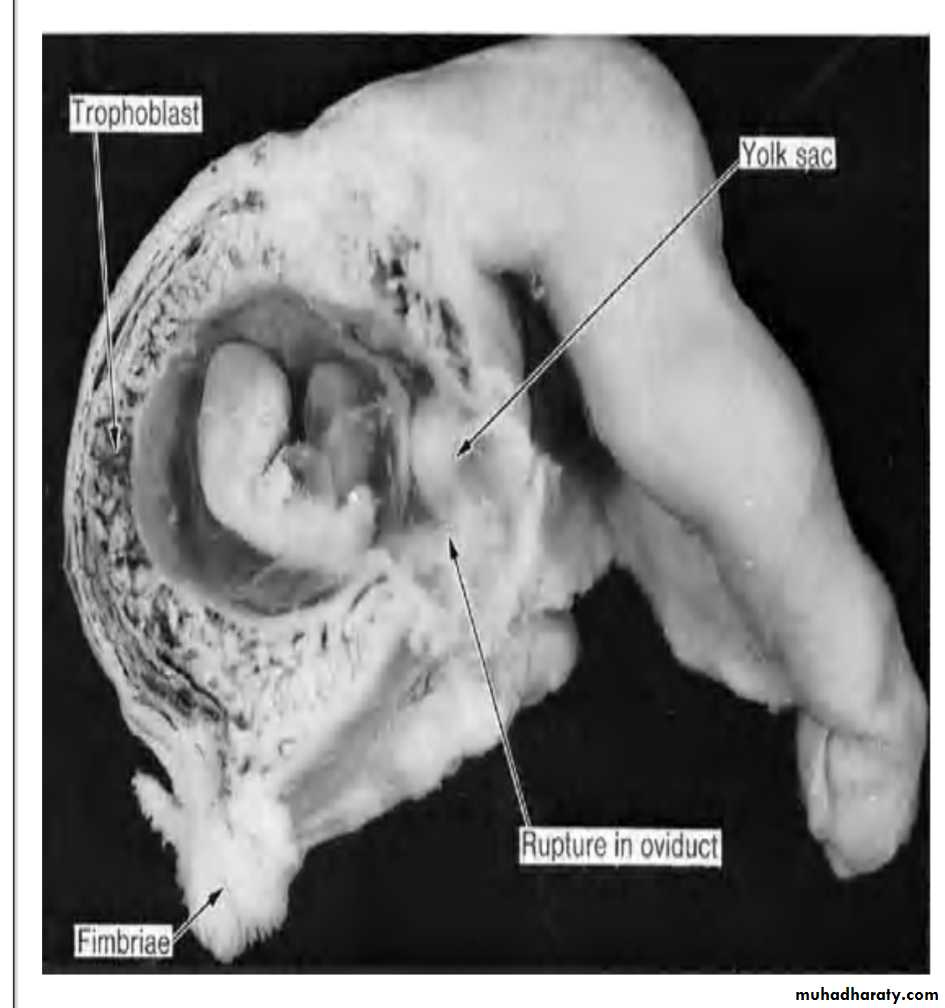

Clinical Correlates Abnormal Implantation of the blastocyst

1. implantation in the abdominal cavity [the ovum most frequently implants in the rectouterine cavity (Douglas pouch) but may implant at any place covered by peritoneum;

2. implantation in the ampullary region of the tube;

3. tubal implantation;

4. interstitial implantation, e.g., in the narrow portion of the uterine tube;

5. implantation in the region of the internal os, frequently resulting in placenta previa; and

6. ovarian implantation.

Abnormal implantation sites